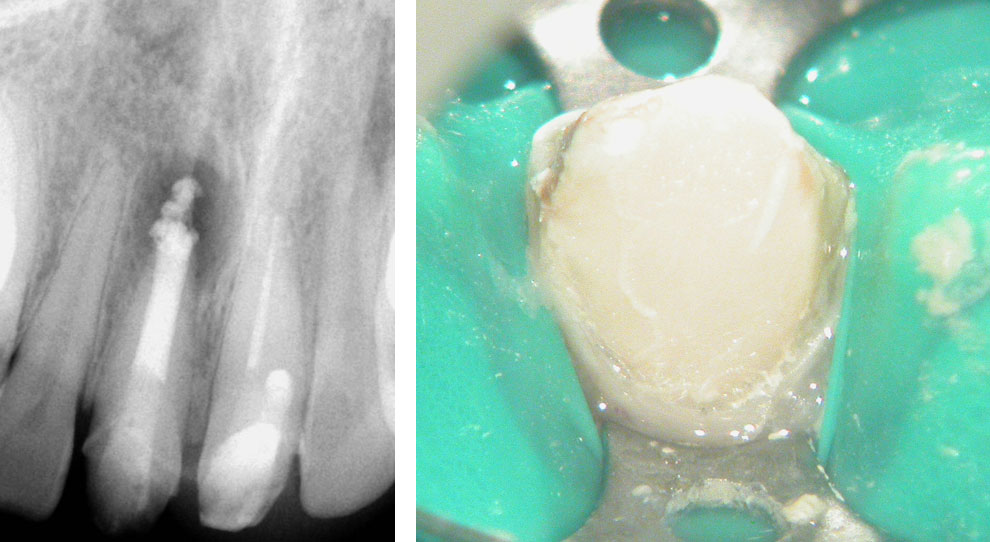

Pre-op:

Central incisor referred after previous clinician had accessed the tooth and was unable to locate the calcified canal.

Removal of temporary restoration shows palatal perforation (red arrow) and a calcified canal in the middle (yellow arrow)

Palatal perforation was supra-crestal and was repaired with GIC

Calcified canal located

Calcium hydroxide placed

Recall after 10 days. Sinus tract healed

Post-op & 1 year recall